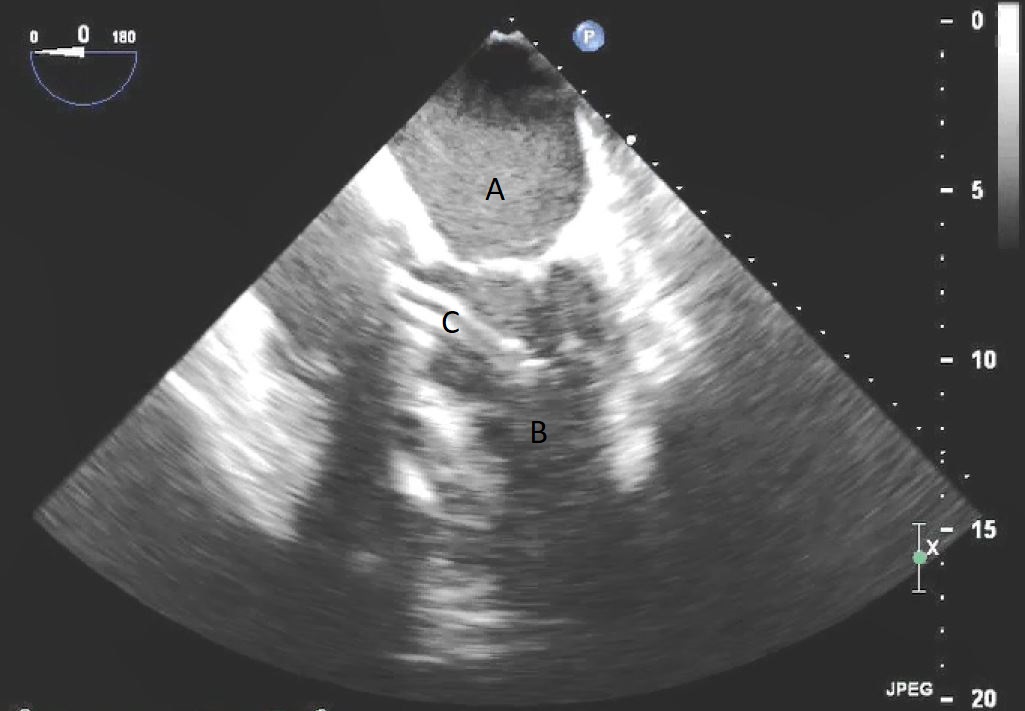

After initial access is obtained with a guidewire, TEE can confirm placement of the guidewire within the aorta and ensure there is no iatrogenic dissection from the procedure. The midesophageal long axis and 4 chamber views can be used to visualize the guidewire crossing of the aortic valve and positioning within the LV cavity. The wire tip should point towards the LV apex. Wire placement too deep within the LV can trigger ventricular arrhythmias and tethering of the mitral valve or subvalvular apparatus should be avoided as this can result in the inlet abutting the mitral valve or damage to subvalvular apparatus (Figs. 3,4) [13]. When the proceduralist is advancing the Impella over the guidewire, the best view to observe the device crossing the aortic valve is the midesophageal long axis view [13].

Impella (A) in the LV cavity caused disruption and damage to subvalvular apparatus resulting in flail segment (B) of the mitral valve.

Fig. 4.Impella (A) placement causing disruption and damage to subvalvular apparatus resulting in mitral valve flail (B) and mitral regurgitation (C).